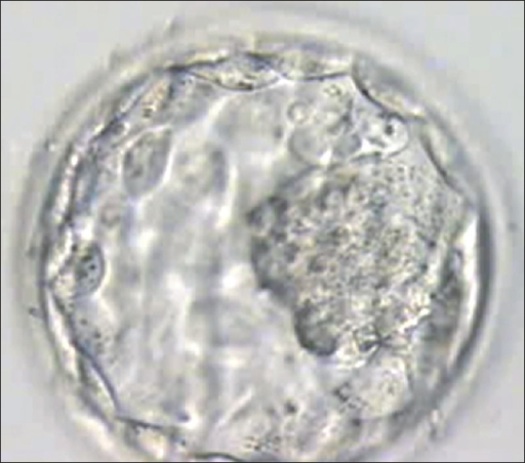

Human cloning has arrived. For the first time, scientists have made an embryonic clone of a person, using DNA from that person’s skin cells. In the future, such a clone could be a source of stem cells, for super-personalized therapies made from people’s own DNA.

Now, Mitalipov and his team have made clones using the same basic technique that created Dolly the cloned sheep in 1996. The scientists took skin cells’ nuclei—the centers of the cells, where the cells keep their DNA—and transplanted them into eggs that had their own genetic material removed. They then grew the eggs for a few days, harvested the daughter cells that appeared, and created a cell line, or a colony of cells that reproduces stably. The stem cells in the cell line could become several different types of adult cells, just like natural stem cells.